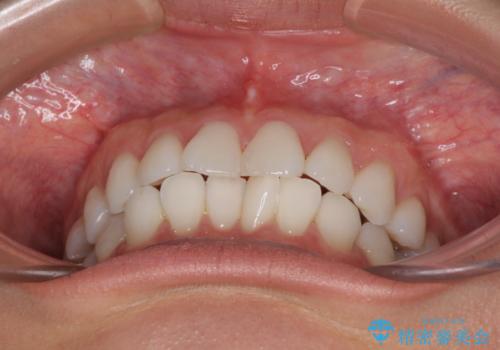

- 前歯のデコボコを気にして来院された患者様です。

海外に留学をされており、卒業後はしばらく日本にいるものの、再び就職のため出国するとのことでした。

定期的に日本に戻ってくる予定であるため、来院頻度の少ないインビザラインにて矯正治療を行うこととしました。

歯列不正が軽度であり、インビザラインの装着時間を遵守してくださったため、日本と海外を行き来しながらも2年弱でしっかりと仕上げることができました。